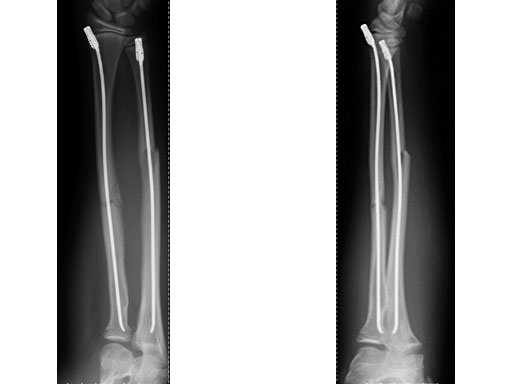

Case 1: Transverse forearm, shaft fracture (22D/4.1), 9-year-old girl.

Case provided by Theddy Slongo, Bern, Switzerland